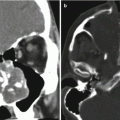

After the roof of the sphenoid and planum are identified (see above), posterior and anterior ethmoidectomy is performed in a posterior-to-anterior direction with the use of 0° and 30° endoscopes. The lowest part of the anterior skull base is the cribriform plate, which is located in the midline between the sphenoid and frontal sinuses (Fig. 10.19). In the pediatric patient, the cribriform is flat and the sinuses are missing (Fig. 10.20).

Stay updated, free articles. Join our Telegram channel